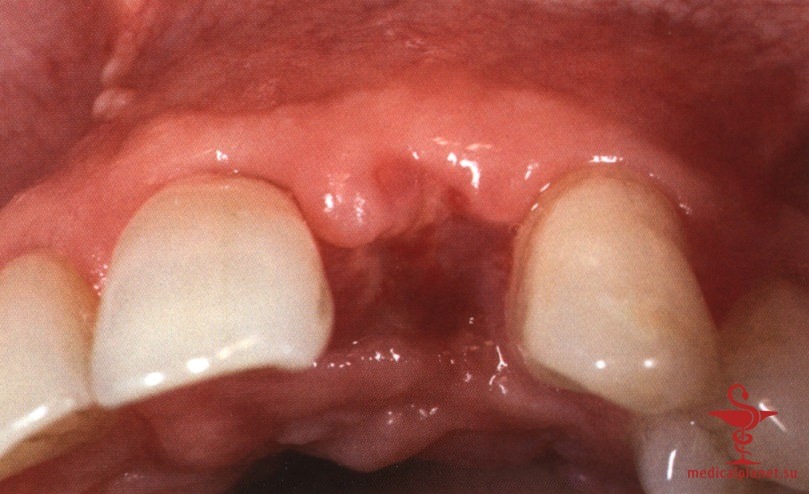

Следует помнить, что любой, даже самый маленький лоскут требует наложения швов в области сосочков, а каждый разрез в этой зоне ведет к уменьшению их высоты, как обсуждалось в отдельной статье на сайте (просим Вас пользоваться формой поиска по сайту выше) (рис. 3). Иными словами, при немедленной имплантации в эстетически значимой зоне нужно избегать отслаивания лоскута.